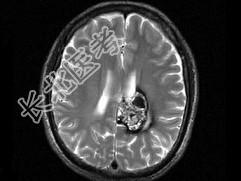

- 单项选择题男,59岁, 反复头晕头痛半年余,重体力活时头痛明显, 根据所提供图像,最可能的诊断是 ( )

A、(左顶)海绵状血管瘤

B、(左顶)室管膜瘤

C、(左侧脑室)胶质瘤

D、(左侧脑室)脉络膜乳头状瘤

E、(左顶)动静脉血管畸形